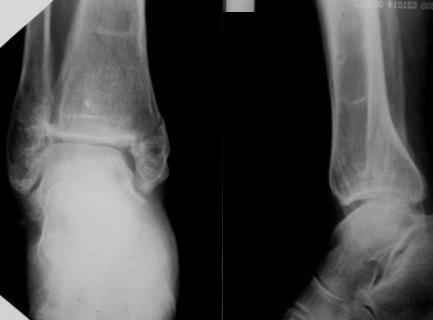

Огромное спасибо всем, кто участвует в обсуждении случая! Приношу глубочайшие извинения и участникам дискуссии и тем, чье внимание просто отвлек своим сообщением. В цейтноте получилось так, что на форум, необоснованно, отправил свои предварительные соображения. Хронология событий следующая. Пришла больная, на руках тот снимок в гипсе, который я выложил. Рассказала, что в 1999г. ломала на этой-же голени обе кости в средней 1/3. Травма тоже была неадекватно низкоэнергетическая - стояла на остановке, шагнула, оступилась - оскольчатые переломы обеих костей. Пластина на большеберцовую. Сросталось долго, линии перелома прослеживались на протяжении 5 лет. Теперешний перелом после того как оступилась в квартире.

Я порассуждал о том, что у нее есть, видимо, системные проблемы с прочностью костей и это МОЖЕТ СУЩЕСТВЕННО ПОВЛИЯТЬ НА ВЫБОР МЕТОДА ОПЕРАТИВНОГО ЛЕЧЕНИЯ, вплоть до артродеза. Предложил начать с замены гипсовой повязки и репозиции для уменьшения отека, столь ее беспокоившего. Которую и выполнил. При попытке R-контроля выяснилось, что кабинет в данный момент обесточен на неопределенный срок. Отправив больную домой я, некорректно по форме, материализовал свои соображения в виде предыдущего сообщения на Форуме.

Посмотрели снимки после репозиции - не понравилась зона синдесмоза.

Сделали 3/4-е - впечатление, что в 99-том там что-то было. На